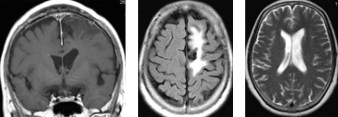

錐体斜台部髄膜腫

この部位は脳神経がすだれのように走行しており、腫瘍により脳幹・脳神経(外転神経・顔面神経・聴神経など)が圧迫されると物が2つに見えたり、耳が聞こえなくなったり、さらに腫瘍のサイズが大きくなると生命に危険な状態となります。

(術前MRI)

(術後MRI)

このように比較的大きい腫瘍が脳幹を圧迫している場合は、重篤な症状をきたし生命に危険が伴う可能性があるため、早急に手術が必要です。

一方、この腫瘍は小さいのですが、三叉神経の圧迫により耐えがたい顔面痛により発見された髄膜腫です。当初手術を躊躇し鎮痛剤を服用しながら経過観察しておりましたが、症状が改善されなかったため、手術を行いました。腫瘍は全摘され、術前に鎮痛剤で改善しなかった顔面痛は、術後には完全に消失しました。勿論、鎮痛剤を服用する必要も全くなくなりました。思い切って手術を決断してよかったと大変満足いただけました。 このように手術をしないと症状が改善されない髄膜腫もあります。